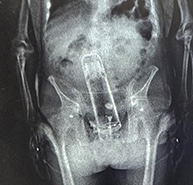

- Non-Binary Person Who Wants Penis AND Vagina Seeks Publicly-Funded Surgery